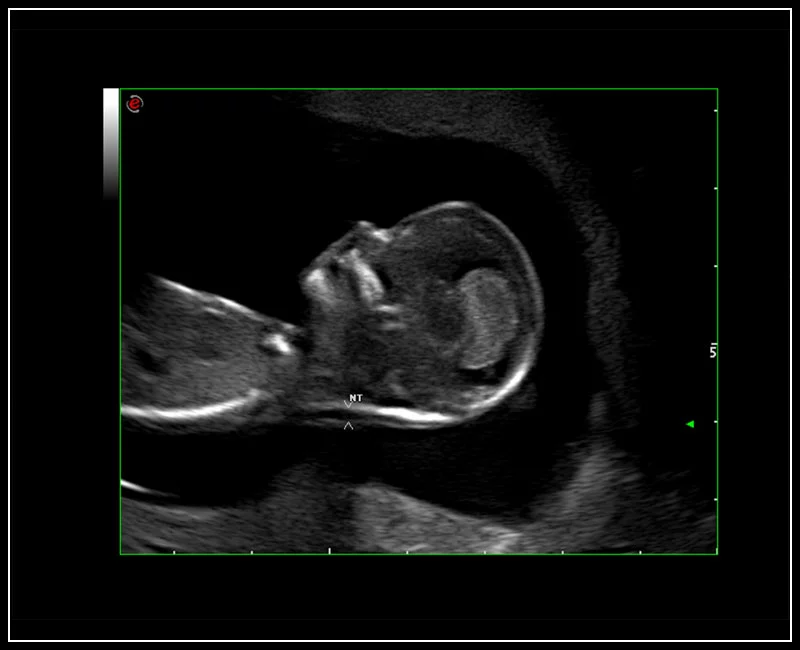

MyLab™9 Platform - HD Zoom on fetus profile with AutoNT measurement

MyLab™9 Platform - HD Zoom on fetus profile with AutoNT measurement